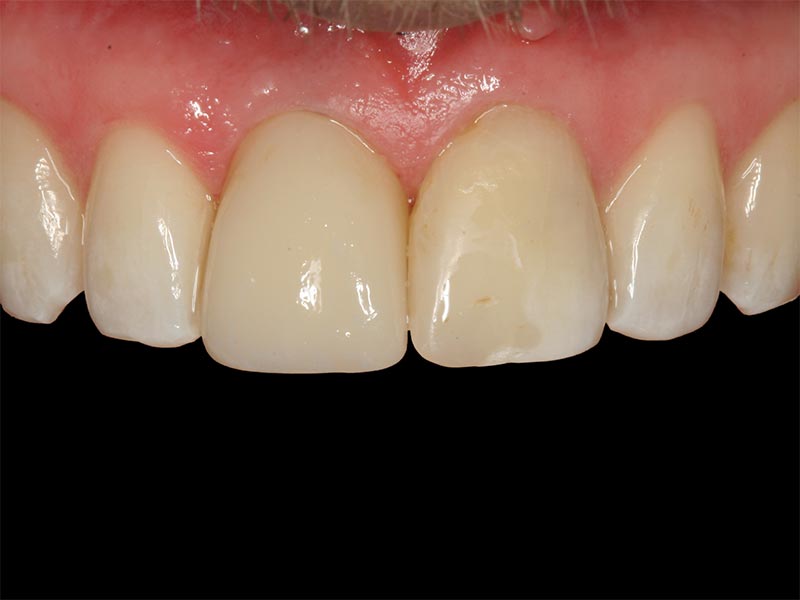

Zahnimplantate werden anhand von moderner virtueller 3D-Planung passgenau geplant und inseriert. Der Vorteil von Implantaten besteht darin, dass festsitzender ästhetischer Zahnersatz auch in solchen Fällen realisiert werden kann, in denen sonst nur herausnehmbare Prothesen möglich wären. Zudem ist im Gegensatz zur Brückenprothetik kein Beschleifen der Nachbarzähne notwendig.

Unter dentalen Implantaten versteht man im allgemeinen eine Schraube, die dort, wo ein oder mehrere Zähne verloren gegangen sind, in den Kieferknochen "eingepflanzt" wird. Diese Therapieform der Implantologie hat sich in den letzten Jahren zu einem alltäglichen Therapieverfahren in der Zahnheilkunde entwickelt. Wissenschaftliche Untersuchungen zeigen hierfür eine Erfolgsquote von i. d. R. 80-98 % über 10 Jahre. Verglichen mit anderen zahnärztlichen Maßnahmen gibt es nahezu keine andere Therapie mit derart guten Erfolgsaussichten. Auch eine Verbesserung der Lebensqualität wird durch implantatgetragenen Zahnersatz laut klinischer Studien erreicht.

Mittlerweile hat sich die Implantologie zu einem alltäglichen Therapieverfahren mit sehr guten Erfolgsaussichten in der Zahnheilkunde entwickelt. Bei guter Mundhygiene und regelmäßigen Kontrolluntersuchungen können fachmännisch gesetzte Zahnimplantate ein Leben lang halten.